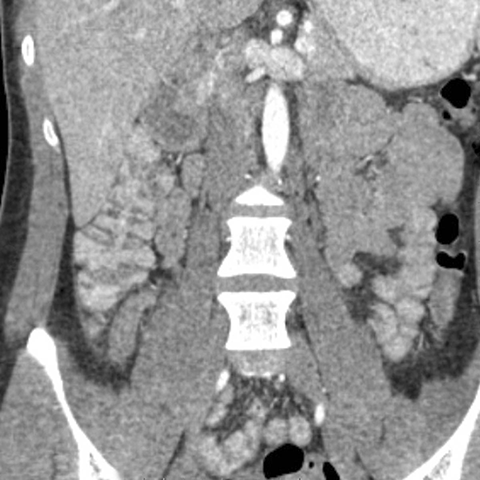

18 year-old male presents with a sudden onset of RLQ pain and rebound tenderness. [4 of 5]